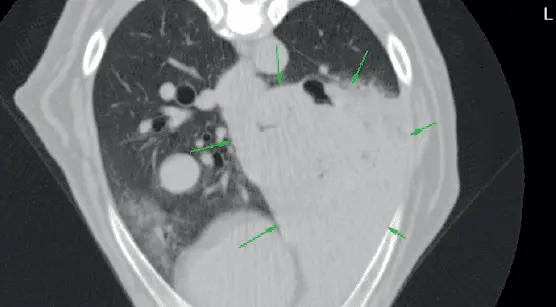

Wykonano tomografię komputerową przed i po podaniu jodowego środka kontrastowego. Na obrazach przedkontrastowych widoczna była duża, dość dobrze widoczna masa tłumienia tkanek miękkich o średnicy 10–20 cm w środkowej części lewego tylnego płata płuca. Masa była rozszerzalna, co powodowało zniekształcenie i przemieszczenie sąsiednich oskrzeli. Tkanka płuca lewego tylnego i lewego przedniego była częściowo zapadnięta. Brak zmian w innych płatach płuc. Węzły chłonne tchawiczo-oskrzelowe i śródpiersiowe nie były powiększone. Brak nieprawidłowości dotyczących opłucnej.

Na zdjęciach pokontrastowych widać było łagodne wzmocnienie poprzednio opisanej masy płucnej. Tomografia potwierdziła zmianę o charakterze pierwotnego nowotworu płuc w lewym tylnym płacie płucnym powodującą niedodmę tego płuca z możliwością krwawienia do oskrzelików (zdj. 5 i 6).